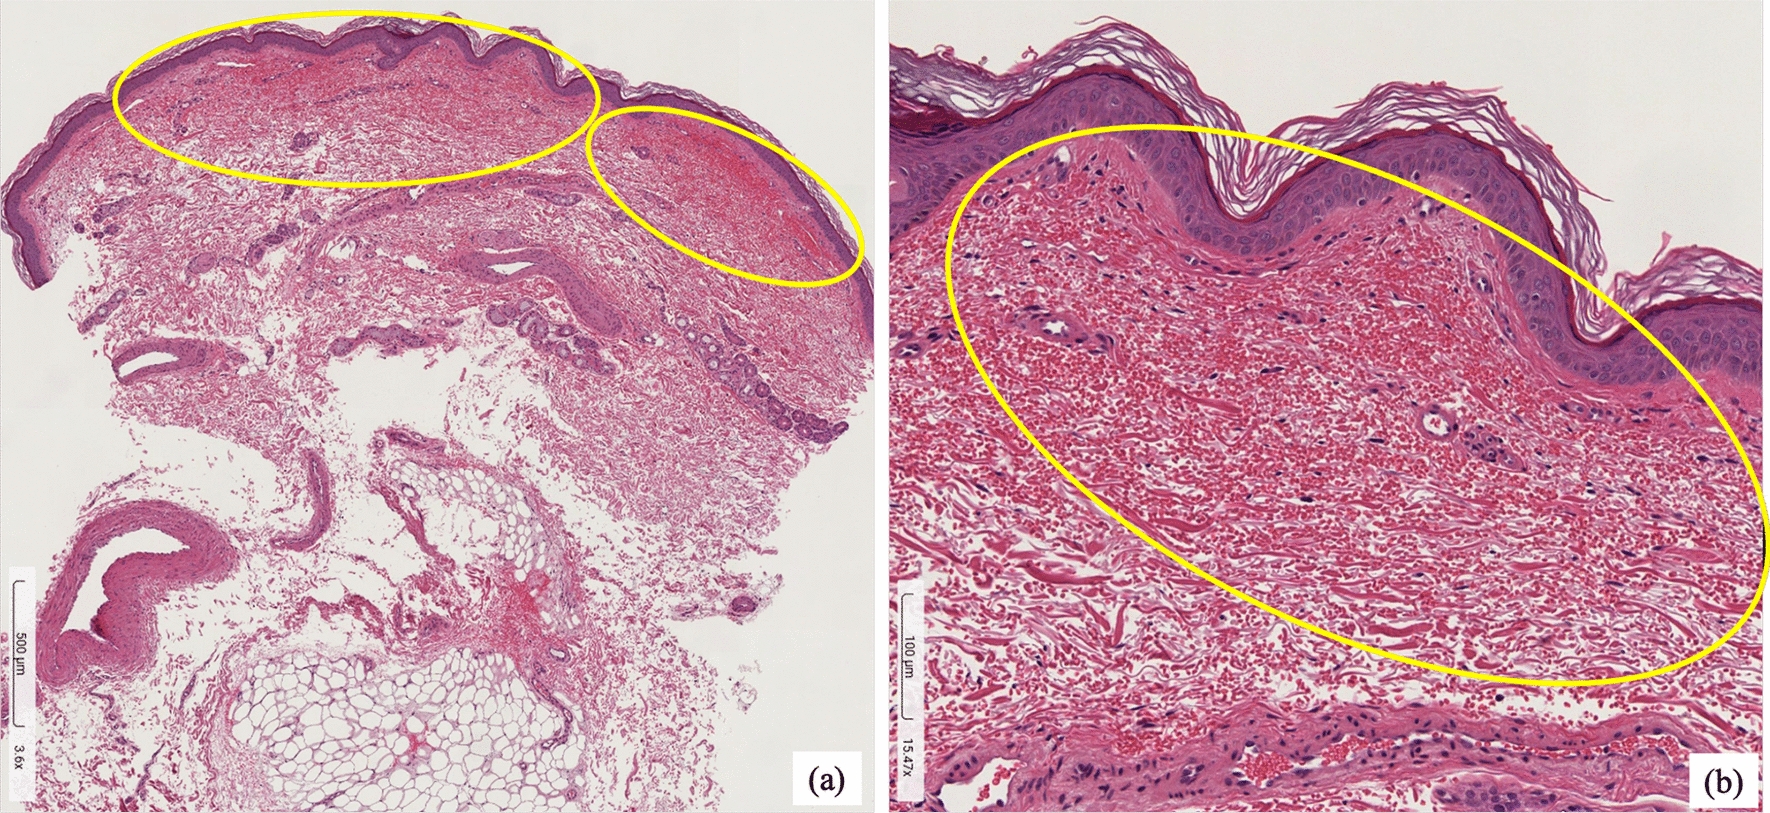

Fig. 2

Histopathological examination revealed erythrocyte extravasation in the subcutaneous tissue (circle), consistent with subcutaneous hemorrhage. There was no evidence of vasculitis, such as inflammatory cell infiltration or fibrinoid necrosis